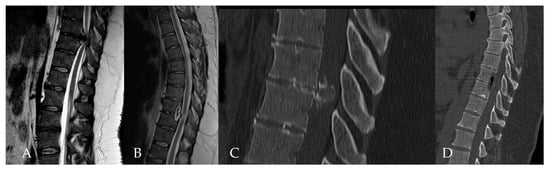

- Yuan, L.; Chen, Z.; Liu, Z.; Li, W.; Sun, C.; Liu, X. Clinical and radiographic features of adult calcified thoracic disc herniation: A retrospective analysis of 31 cases. Eur. Spine J. 2023, 32, 2387–2395. [Google Scholar] [CrossRef] [PubMed]